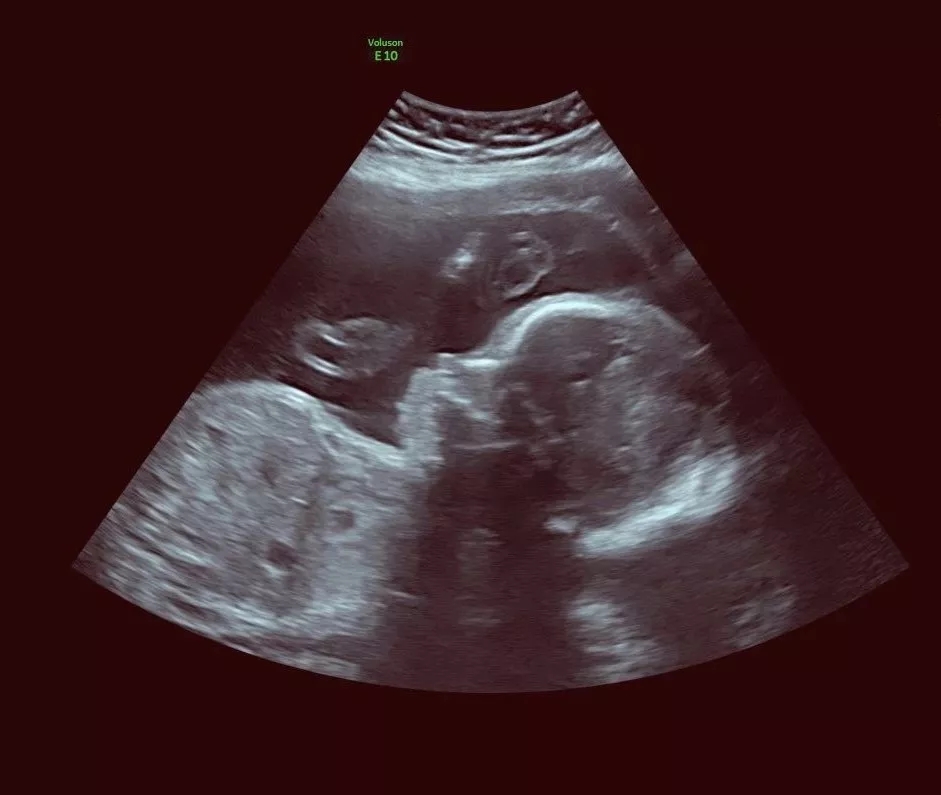

以前在當?shù)匦l(wèi)生室做二維彩超,

只能看出個輪廓。

接下來,小編從三張圖

帶大家了解一下

二維、三維、四維的效果!

這僅僅只是最基礎的區(qū)分,

別看這只是數(shù)字上多了“1”,

優(yōu)點多得可不止“一個”呢。